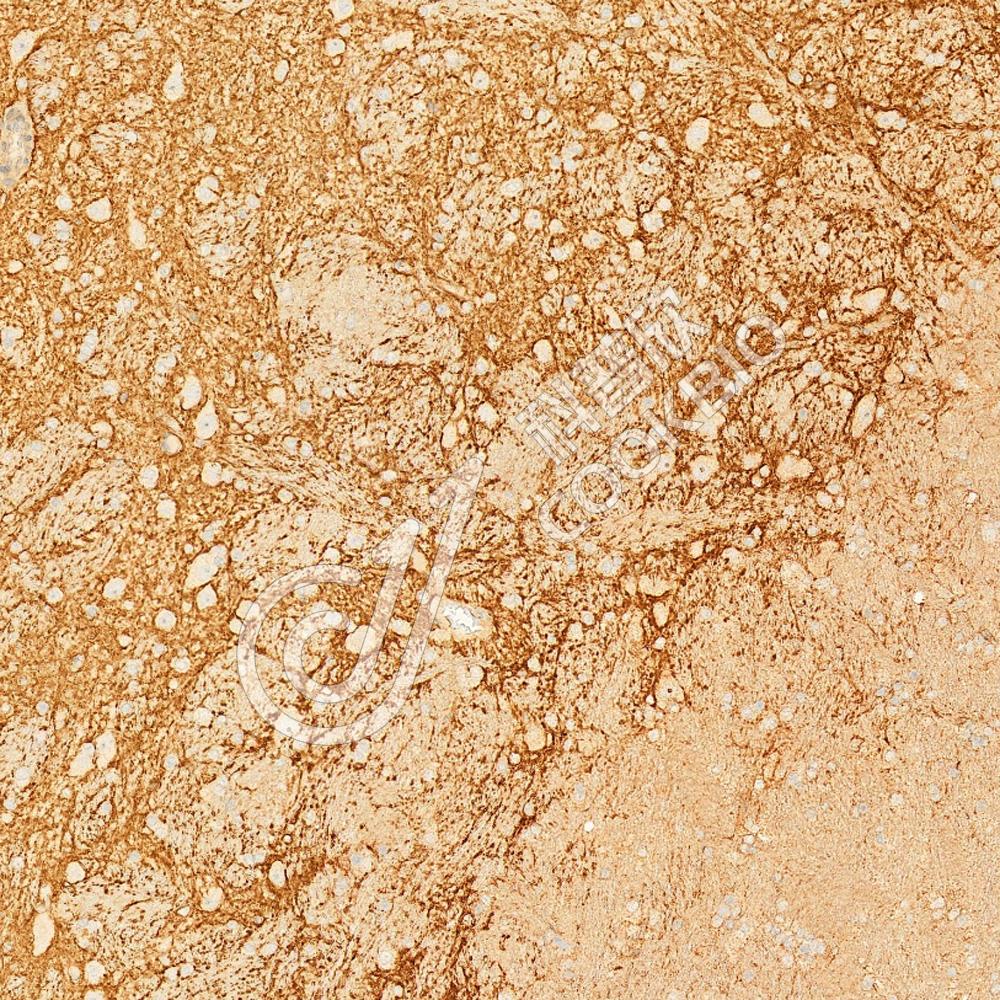

IHC检测GABA Transporter 3/GAT 3蛋白(货号 K1345327).

样品: 大鼠脑, 4%多聚甲醛 (货号KSG1101) 固定12-24小时.

抗原修复: Tris-EDTA抗原修复液(pH 9.0) (KSG1203), 98℃, 20分钟.

—抗: 1: 1300稀释, 4℃ 孵育过夜.

二抗: S-vision免疫组化多聚二抗(山羊抗兔),即用型 (货号KB3906), 室温孵育20分钟.